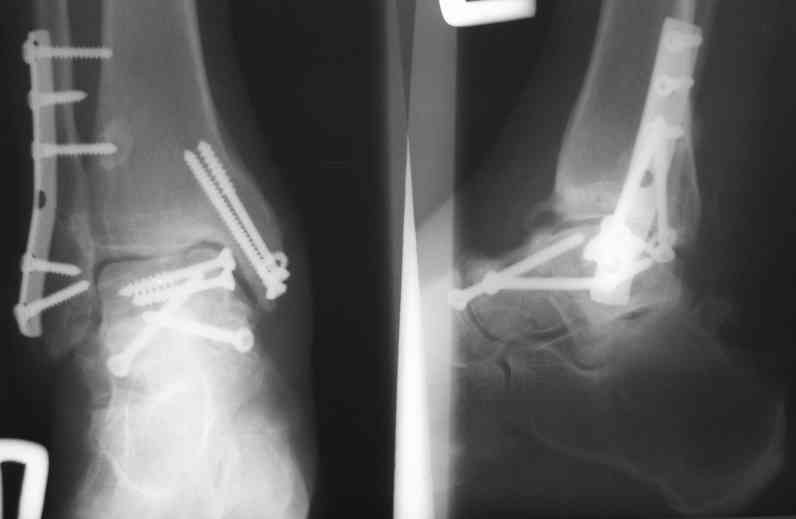

Случай с множественным оскольчатым переломом тарана оперированный из двойного доступа.

Через 2 мес.:

Через 8 мес.:

Через 14 мес.: